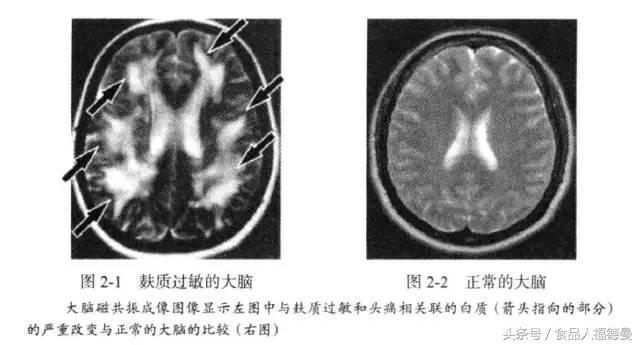

在《谷物大脑》一书中,作者认为是麸质蛋白引起炎症因子,这些因子会直接导致神经退化性疾病,如右边这张非常流行的图。